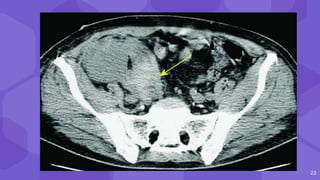

Double contour

23

20 ⬢ Large clinicallysignificant hematomas- 4-8% ⬢ C/F Red blood cell count Peritransplant Subcapsular ● Double contour ● Compression of renal collecting system, vascular pedicle

• #23  Subcapsular hematomas sign of ‘double contour’ of the kidney